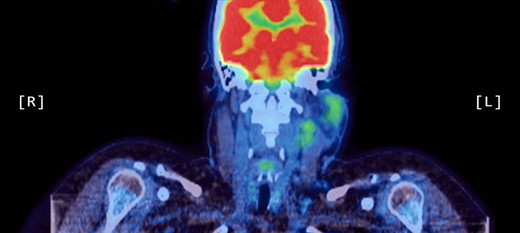

A positron emission tomography (PET) scan was subsequently arranged, which demonstrated increased uptake of the left parotid gland and several enlarged lymph nodes in the neck bilaterally (Figs 1 and 2).

Coronal PET scan showing increased uptake of the left parotid gland and enlarged left-sided lymph nodes in the neck.